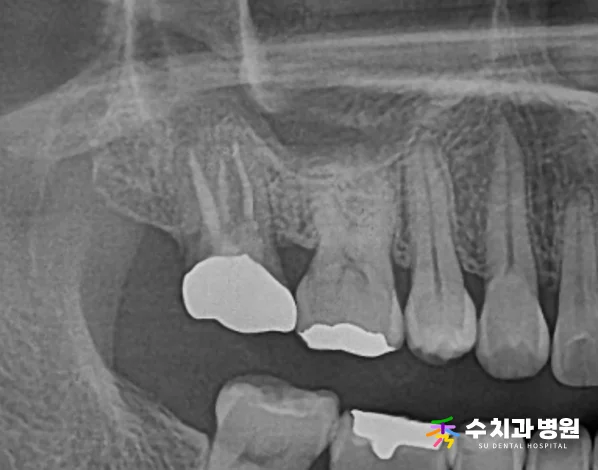

[📸 치료 후 엑스레이] (촬영일: 2023년 10월)

3️⃣ 신경관 충전 및 레진 코어 수복

신경관 내 염증이 안정적으로 조절된 것을 확인한 후,

빈 공간을 치과용 재료로 꼼꼼히 밀폐하고

레진 코어로 단단하게 채워 수복을 완료했습니다.

✨ 치료 후

치료를 성공적으로 마무리한 후,

환자분께서 내원 당시 호소하셨던

잇몸의 고름주머니와 불편감이 사라졌습니다.